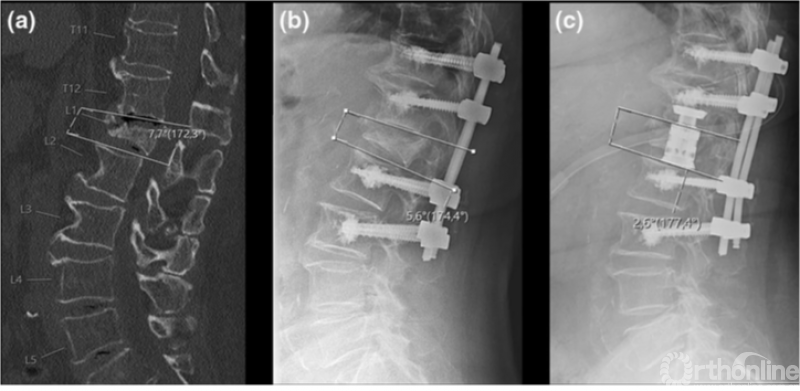

骨质疏松性椎体骨折的分型也有更多研究,常用分型有郝定均的《胸腰椎骨质疏松性骨折评分系统》和《德国骨科及创伤协会的骨质疏松性骨折分型》,近年论文显示两种分型均表现出良好的可信度和可靠性[5, 6]。

德国骨科及创伤协会的骨质疏松性骨折分型